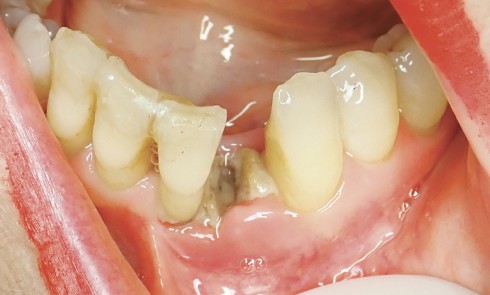

Article réservé à nos abonnés Ostéonécrose péri-implantaire mandibulaire liée aux médicaments : un rapport de cas

RÉSUMÉ L’ostéonécrose des maxillaires liée aux médicaments (MRONJ) est définie comme un effet indésirable des médicaments antirésorptifs ou antiangiogéniques. Ce rapport...

Article réservé à nos abonnés Comment traiter les ostéonécroses des mâchoires ? Traitement médical ou chirurgical ?

En 2014, l’American Association of Oral and Maxillofacial Surgeons (AAOMS) [1] a défini les critères de diagnostic de l’ostéonécrose (tableau 1), les...